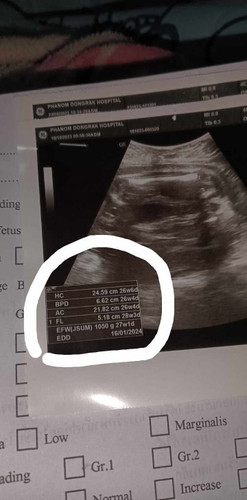

สอบถามคะ 1050g คือน้ำหนักปริมาณลูกใช่มั้ยคะ

ใช้คะ 1050g